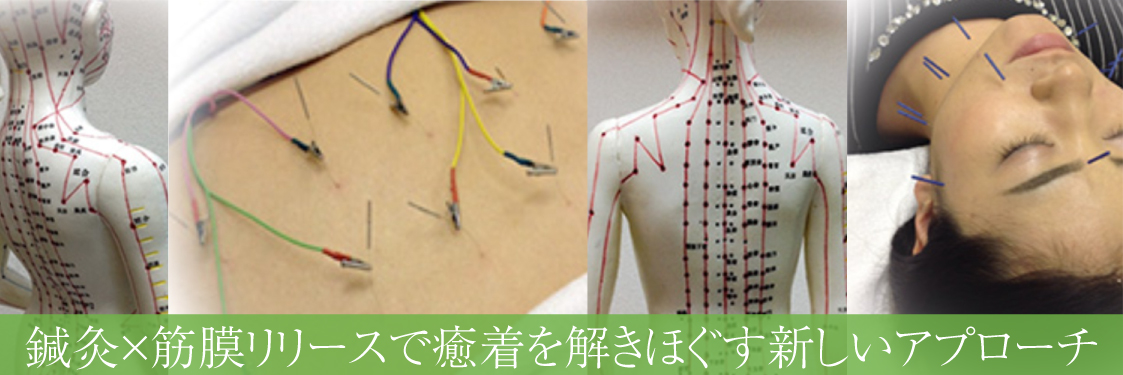

筋膜の癒着を解放する|鍼灸と筋膜リリースの融合

鍼灸で癒着にアプローチ

筋膜リリースと組み合わせて根本からの解放へ

鍼灸と筋膜リリースの融合は、当院が行う施術のなかでも非常に効果的なアプローチです。

鍼灸×筋膜リリースの施術

鍼でアプローチすることで、癒着した部位に微細な刺激を与え、組織を解放するきっかけを作ります。

さらに手技による筋膜リリースで、圧迫されていた部分の血流や神経の流れが改善し、痛みや動かしにくさが緩和されます。